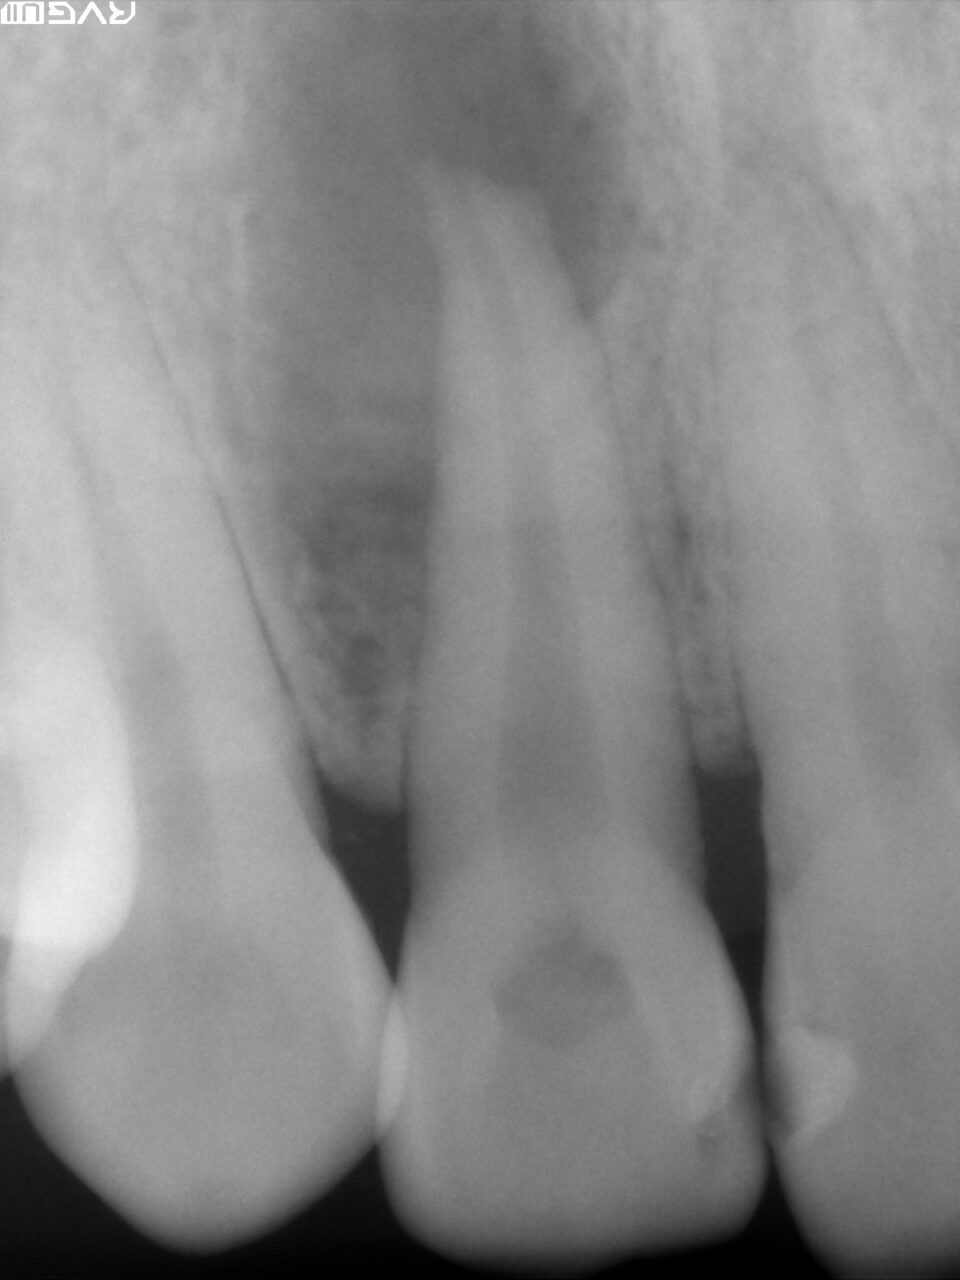

患者は医療従事者で、噛むと違和感があると訴えていたので、取り敢えず術前の修復物を除去してフルクラウンの仮歯を装着して様子を診ていたが、自発痛が出てきたために抜髄処置を行うことになりました。

術前のレントゲン:近心頬側根に炎症があるように観えます。